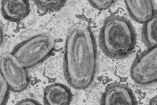

Así luce el virus de la viruela del mono en el microscopio

Fotos de la viruela del mono visto desde un microscopio se han vuelto virales desde el aumento de los contagios de esta enfermedad.